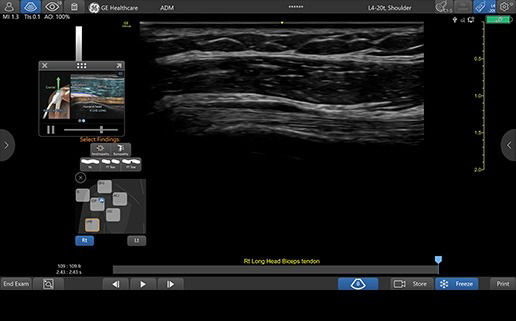

VENUE COACH MSK

Simplifying MSK scans

This easy-to-use exam documentation tool assists users through exams by providing reference images and anatomy markups. Multiple anatomical areas and helpful video tutorials help clinicians to acquire the scans they need.

• MSK Diagrams: Simplifies documentation and assists the clinician in follow up for patients. No need to manually type findings—you can simply assign a label from a pre-populated list that correlates with the images. Get a single view diagram with one click image storing, keep track of assessments and show trends in response to therapy.

• Reference Image: Reference image provides anatomy mark-ups to assist novice users in scanning the correct anatomy

• Bilateral mode: Helps you to view the opposite side of the same zone for comparison (available for Shoulder preset)